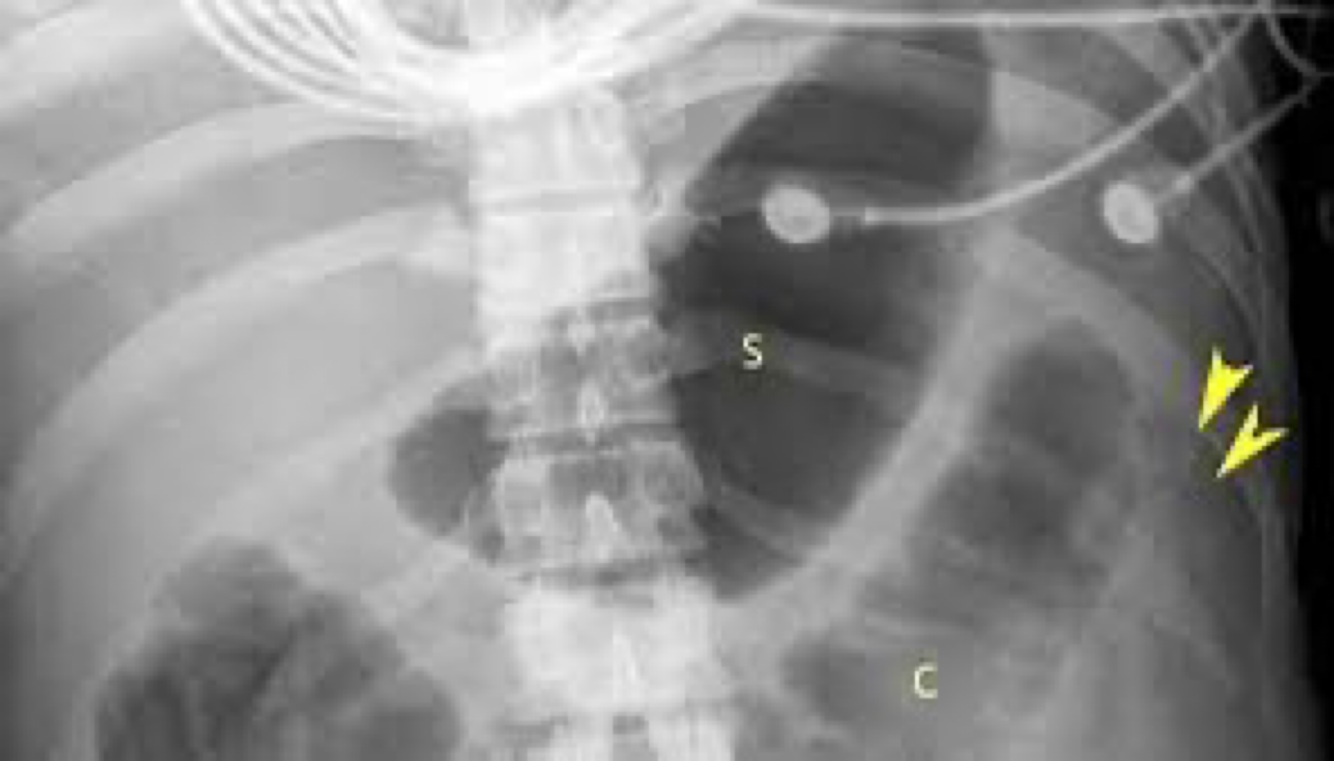

What disease has a thumbprint x-ray?

A

Toxic megacolon